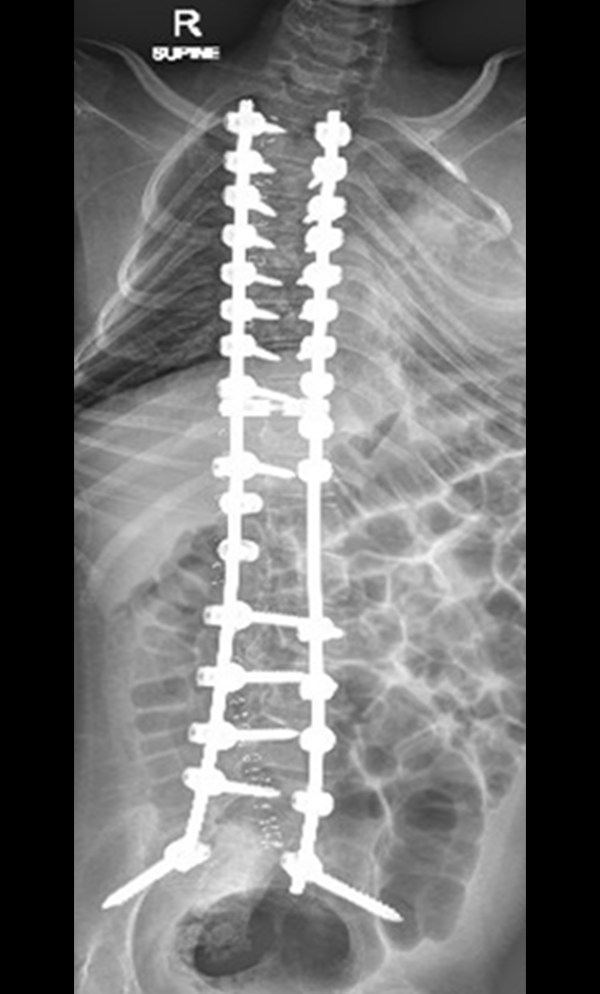

Gallery : Before - After